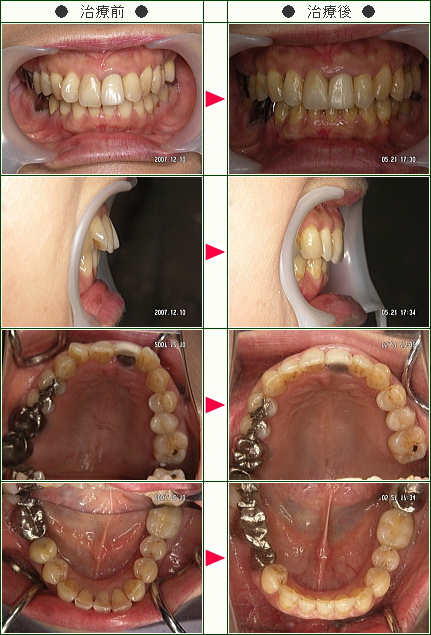

「周りの友達には「この歳になってなんで?」と驚かれました」M・M様 61歳 女性

元々歯並びは良いとは言えませんでしたが、悪いなりに左右対称で子供の時は笑うと八重歯がかわいいなどと言われ、全く気にしてはいませんでした。

しかし、60才頃から対称が崩れ、デコボコの全く不規則な並びが顕著になり、かわいい八重歯どころか鬼歯の様相を呈して来ました。

かかりつけの歯医者さんが、この傾向はますます進むと言った時、矯正を決意しました。

周りの友人達には「この年齢になってなんで?」と驚かれました。

近所で矯正歯科に複数話を聞きに行きましたが、治療法も期間も料金も全く異なり迷いました。

一番嫌だと思ったのは、どちらも真ん中から4番目の歯を上下左右計4本抜くと言われた事です。

そこで図書館から歯列矯正の本を借り読みました。

そこで南青山デンタルクリニックの青山先生の本と出会い、近年の抜かない矯正を知り、その治療方針、姿勢に心配もふっとび、ここなら安心と開始しました。

当時、骨粗しょう症の治療薬を飲んでおり抜歯の際のリスクの相談、初めてブラケットを装着した後起こった湿疹が金属アレルギーかとの動揺等、何かと心配事の多い私でしたが、青山先生のいつも落ち着いた誠実な物腰と説明に不安も消え、安心して治療を進める事ができました。

担当の歯科衛生士さんもていねいで、きちんとした仕事ぶりで、治療の折にはいつも痛みを気遣って進めてくれました。

歯垢や歯石も歯茎の中まで除去するのだと初めて知りました。